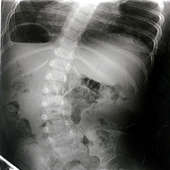

平成19年2月13日

60度で来院

レントゲン平成19年2月13日

60度で来院 1歳11ヶ月

60度

聖隷佐倉市民病院60度

きれいな身体と肋骨変形も改善

レントゲンは正面からです